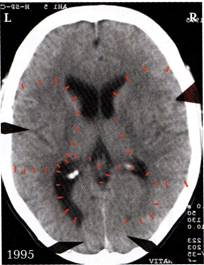

1. ábra: A felső jobb nyíl az  első szexuális konfliktusára utal a jobb oldali birtokzónában, mely másfél éves korában érte őt. A felső bal nyíl a második „szexuális konfliktus”-t mutatja (exhibicionista). Ettől kezdve a kislány skizo-nymphomániás konstellációban volt, biológiai fejlődését tekintve 8 évesen, melyet azonban a terhessége folytán 19 évesen még 3 évvel megnövelhette, így elérte a 11 évet.

első szexuális konfliktusára utal a jobb oldali birtokzónában, mely másfél éves korában érte őt. A felső bal nyíl a második „szexuális konfliktus”-t mutatja (exhibicionista). Ettől kezdve a kislány skizo-nymphomániás konstellációban volt, biológiai fejlődését tekintve 8 évesen, melyet azonban a terhessége folytán 19 évesen még 3 évvel megnövelhette, így elérte a 11 évet.

10 évesen egy szaltó ugrása közben az uszodában, amikor fejét hátul beütötte az ugródeszkába, elszenvedett egy „birtokboszankodás-konfliktus”-t és egy „esés-konfliktus”-t. Egyébként lehet látni mindkét kamra hátsó szarvában a Hameri gócot, a jobb agyféltekén a bal (partnert érintő) petefészket a megoldási fázisban petefészekcisztával, a bal agyféltekén a gyermekre vonatkozó, még aktív Hameri gócot. A két alsó nyíl a „nyakba szakadó konfliktus” reléjére mutat. A Hameri gócok félig aktív, félig megoldási fázisban vannak (= függőben lévő gyógyulás).